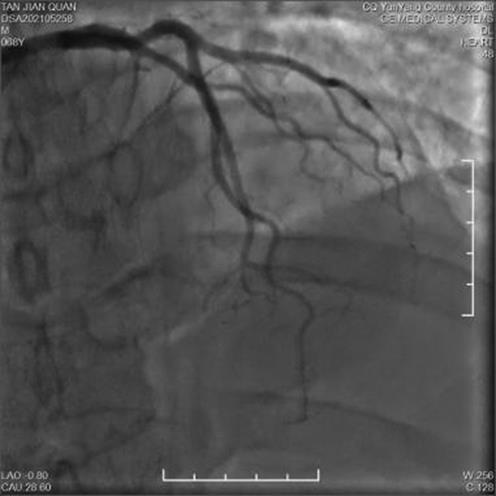

• 疑似雷帕霉素药物洗脱支架术后Kounis综合征1例

2024, 49(1):97-100. DOI: 10.13406/j.cnki.cyxb.003409

摘要 (42) HTML (15) PDF 1.14 M (104) 评论 (0) 收藏

摘要: